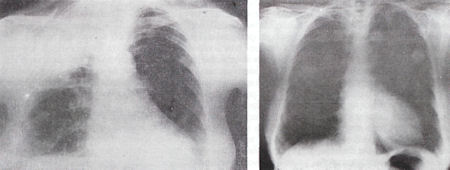

α/α Θώρακος: Πνευμονία δεξιού άνω λοβού. (Είκ. 1).

Ακολουθούν ακτινογραφίες μετά 1 εβδομάδα (Είκ. 2), μετά 25 μέρες και μετά 3 μήνες, οι οποίες ήταν τελείως φυσιολογικές.